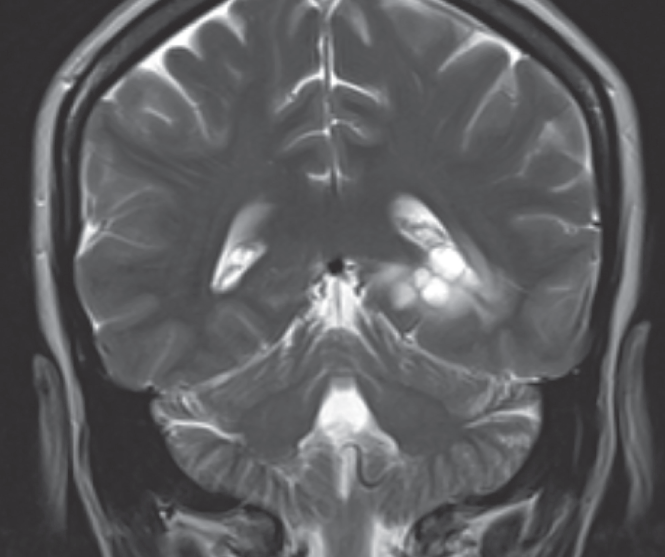

Hanns Frimpong, MS; Ronda D. Edwards, MPH; Syed A.A. Rizvi, PhD, MBA; Sultan S. Ahmed, MD

A 33-year-old Asian American female who came to our practice with her husband complaining of intermittent dizziness and near-syncopal attacks that have been going on for 10 years now.